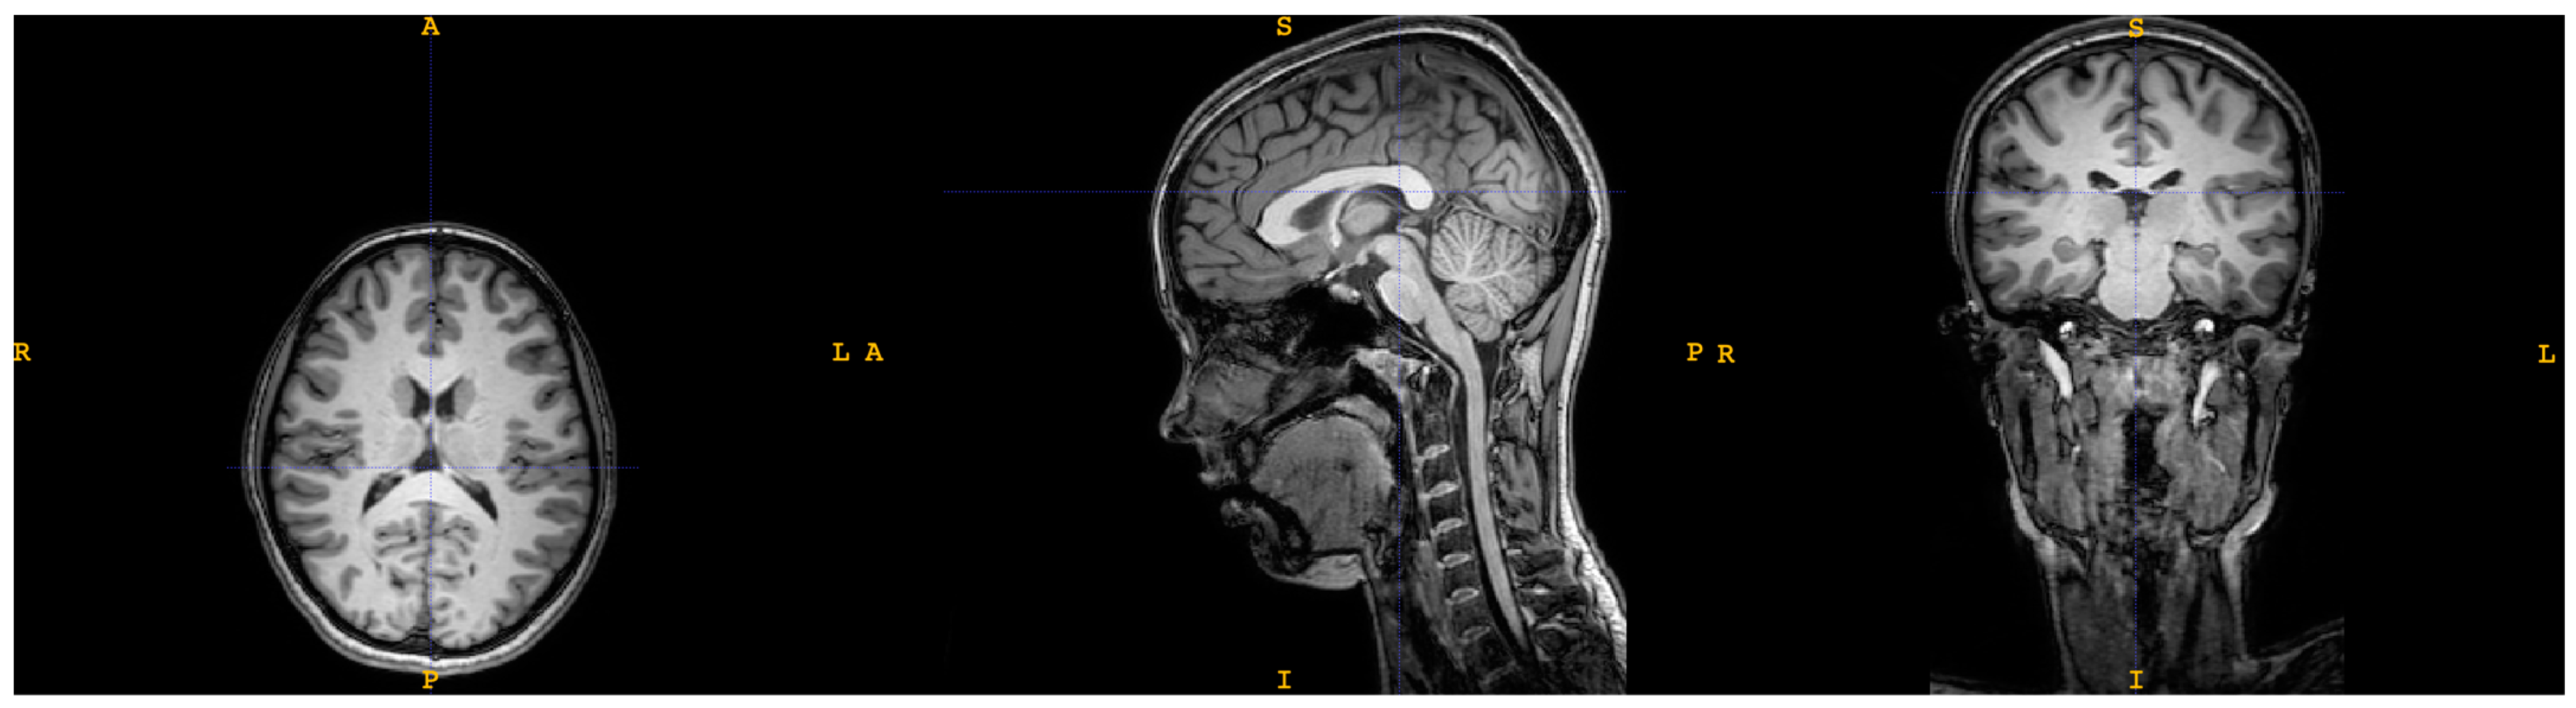

2.1. Magnetic Resonance Imaging (MRI)

2.1.1. Image Processing

| T1 | dMRI | |

| Sequence type | Turbo field echo | Diffusion-weighted single shot spin echo |

| Repetition time | 8.1 ms | 9000 ms |

| Echo time | 3.7 ms | 86 ms |

| Flip angle | 8° | 90° |

| Echo train length | 170 | 59 |

| No. of slices | 240 | 140 |

| B-value | - | 1000 s/mm2 |

| No. of gradient directions | - | 61 |

| Orientation | Sagittal | Axial |

| Acquisition duration | 359 s | 696 s |